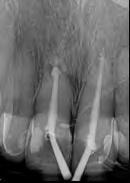

El retratamiento endodóntico del conducto obturado fue realizado con un enjuague final con EDTA 17% pasivamente activado ultrasonicamente, seguido por obturación del conducto radicular usando conos de gutapercha con BIO-C® REPAIR (Angelus - Brasil). BIO-C® REPAIR es un nuevo Cemento Endodóntico Biocerámico Listo para Uso. Puede ser colocado de la jeringa directamente al conducto radicular. Los conos de gutapercha fueron compactados con una técnica de compactación fría vertical (Figura 5).

Figura 5 - Obturación endodóntica

ambientes húmedos, inducción y conducción en la formación de tejidos duros, cementogénesis con consecuente formación de adherencia periodontal normal, hacen el material más adecuado para estas situaciones clínicas. En este caso, se utilizaron nuevos materiales biocerámicos para obturación de la cavidad retrógrada. En primer lugar, el BIO-C® REPAIR (Angelus - Brasil) se utilizó para obturar el espacio en el conducto radicular. Un tapón apical de BIO-C® REPAIR (Angelus - Brasil) fue colocado sobre la raíz, sellando la retro cavidad (Figura 10, Figura 11).

El seguimiento de 6 meses mostró una cicatrización ósea muy rápida. Clínicamente, ya no tenía signos ni síntomas de una enfermedad endodóntica (Figura 12). La cicatrización ósea rápida puede estar relacionada con la liberación de calcio de este nuevo material de reparación biocerámica que contiene tungstato de calcio como radiopacificador en lugar de Óxido de Bismuto de su antecesor (MTA convencional). Además, el tamaño de las partículas biocerámicas son menores que del MTA, permitiendo más contacto con los tejidos circundantes, aumentando la respuesta biológica.